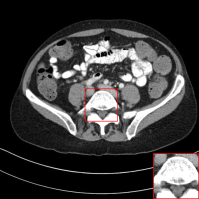

Figure 4: Qualitative results of our method and other baselines on Mayo Clinic Low Dose CT dataset. (a) Real low-dose. (b)-(f) Results of each methods. (g) Real normal-dose. As shown in the highlighted red box, the reconstructed image by our method has few noise and artifacts. The display window is [160,240]160240[160,240] HU.

Table 2: The average PSNR and SSIM results of different methods on Mayo Clinic Low Dose CT dataset. Our results are marked in bold.

Denoising on Low-Dose CT

Since Computed Tomography (CT) helps to diagnose abnormalities of organs, CT is widely used in medical analysis. Reducing the radiation dose in order to decrease health risks causes noise and artifacts in the reconstructed images. Like the real-world noise, the noise distributions of the reconstructed image are difficult to model analytically. Therefore, we adopt a CT dataset authorized by Mayo Clinic [Moen etย al.(2021)Moen, Chen, Holmesย III, Duan, Yu, Yu, Leng, Fletcher, and McCollough] to evaluate the generalization ability of our method on real-world noise. Mayo Clinic dataset consists of paired normal-dose and lose-dose CT images for each patient. The Normal-Dose CT (NDCT) and the Low-Dose CT (LDCT) images correspond to clean and noisy images, respectively. For the training, we obtain 2,850 images in 512ร—512512512512\times 512 resolution from 20 different patients. We construct 1,422 LDCT images from randomly selected 10 patients as a noise set and 1,428 NDCT images from the remaining patients as a clean set for unpaired training. For the test, we obtain 865 images from 5 different patients. As shown in Table 2, our method achieves the best and the second-best performance in PSNR and SSIM, respectively. Note that our model trained on the unpaired dataset outperforms the RED-CNN trained on the paired dataset in PSNR. It indicates that our method can be more practical in medical analysis where obtaining paired datasets is challenging. We also compare the qualitative results with other baselines. As shown in Figure 4, other methods tend to generate artifacts or lose details. On the other hand, our method shows a reasonable balance between noise removal and image quality. More qualitative results are provided in the supplementary material.